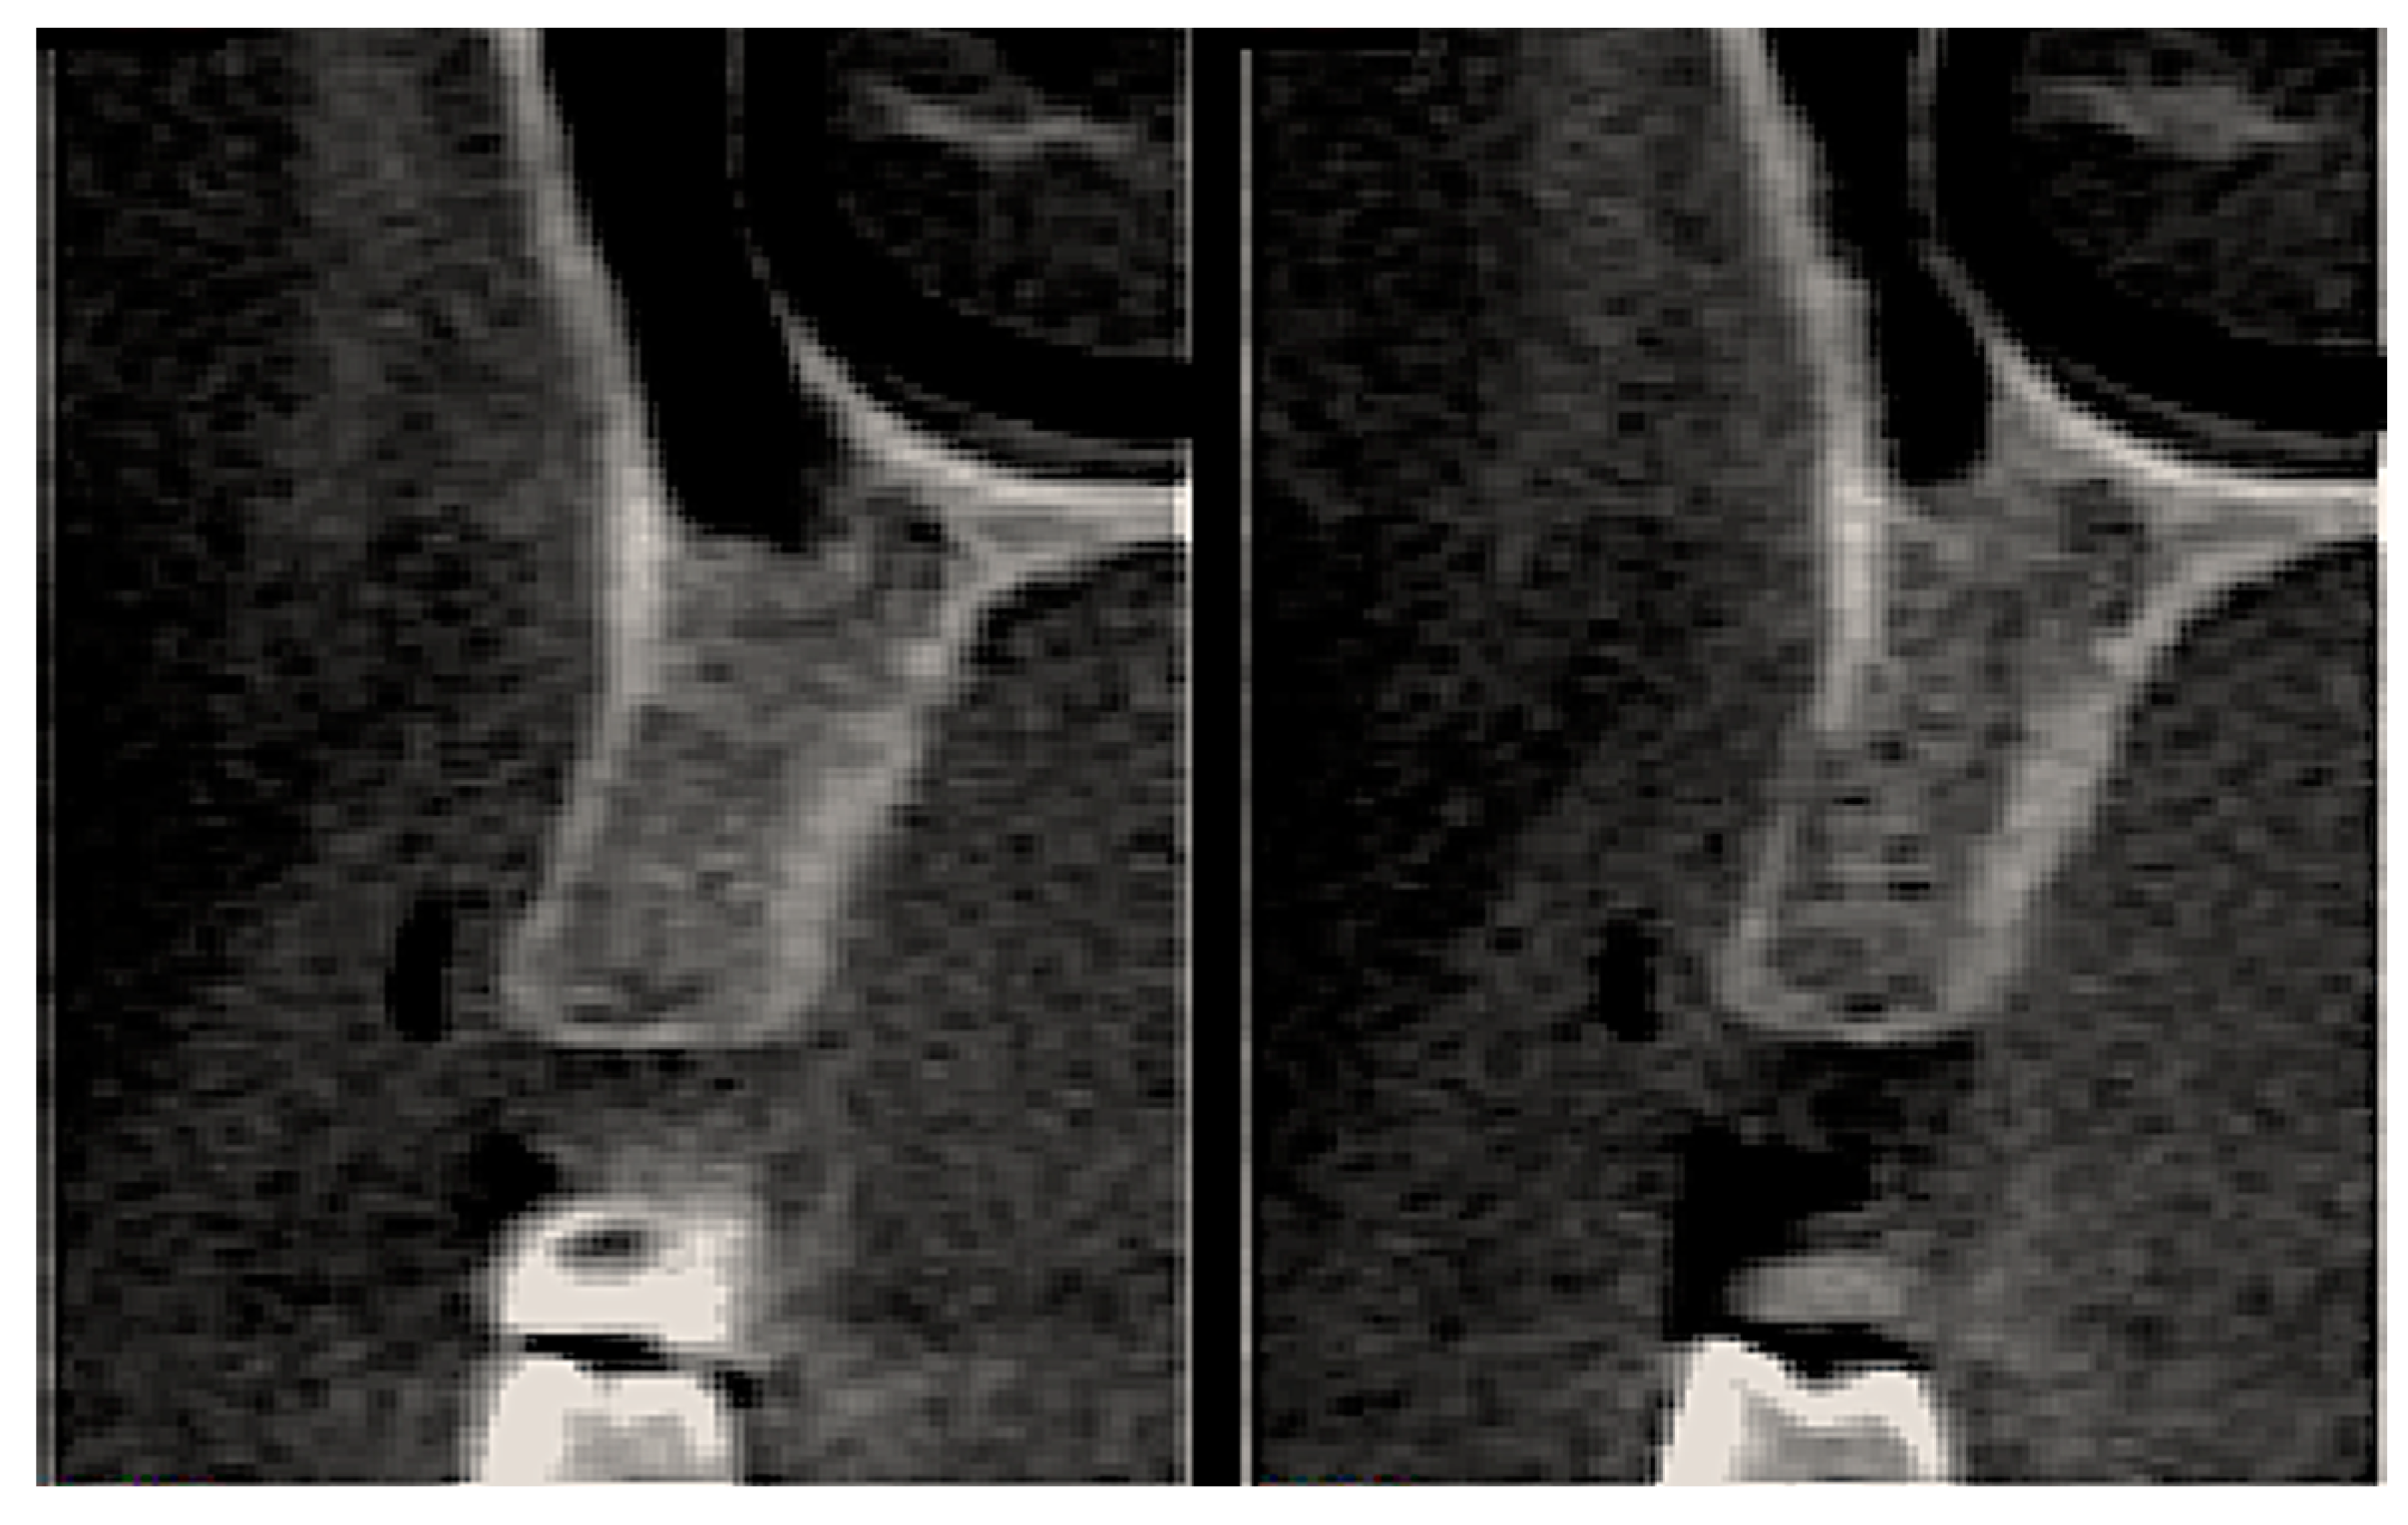

2.6. Tomographic Analysis